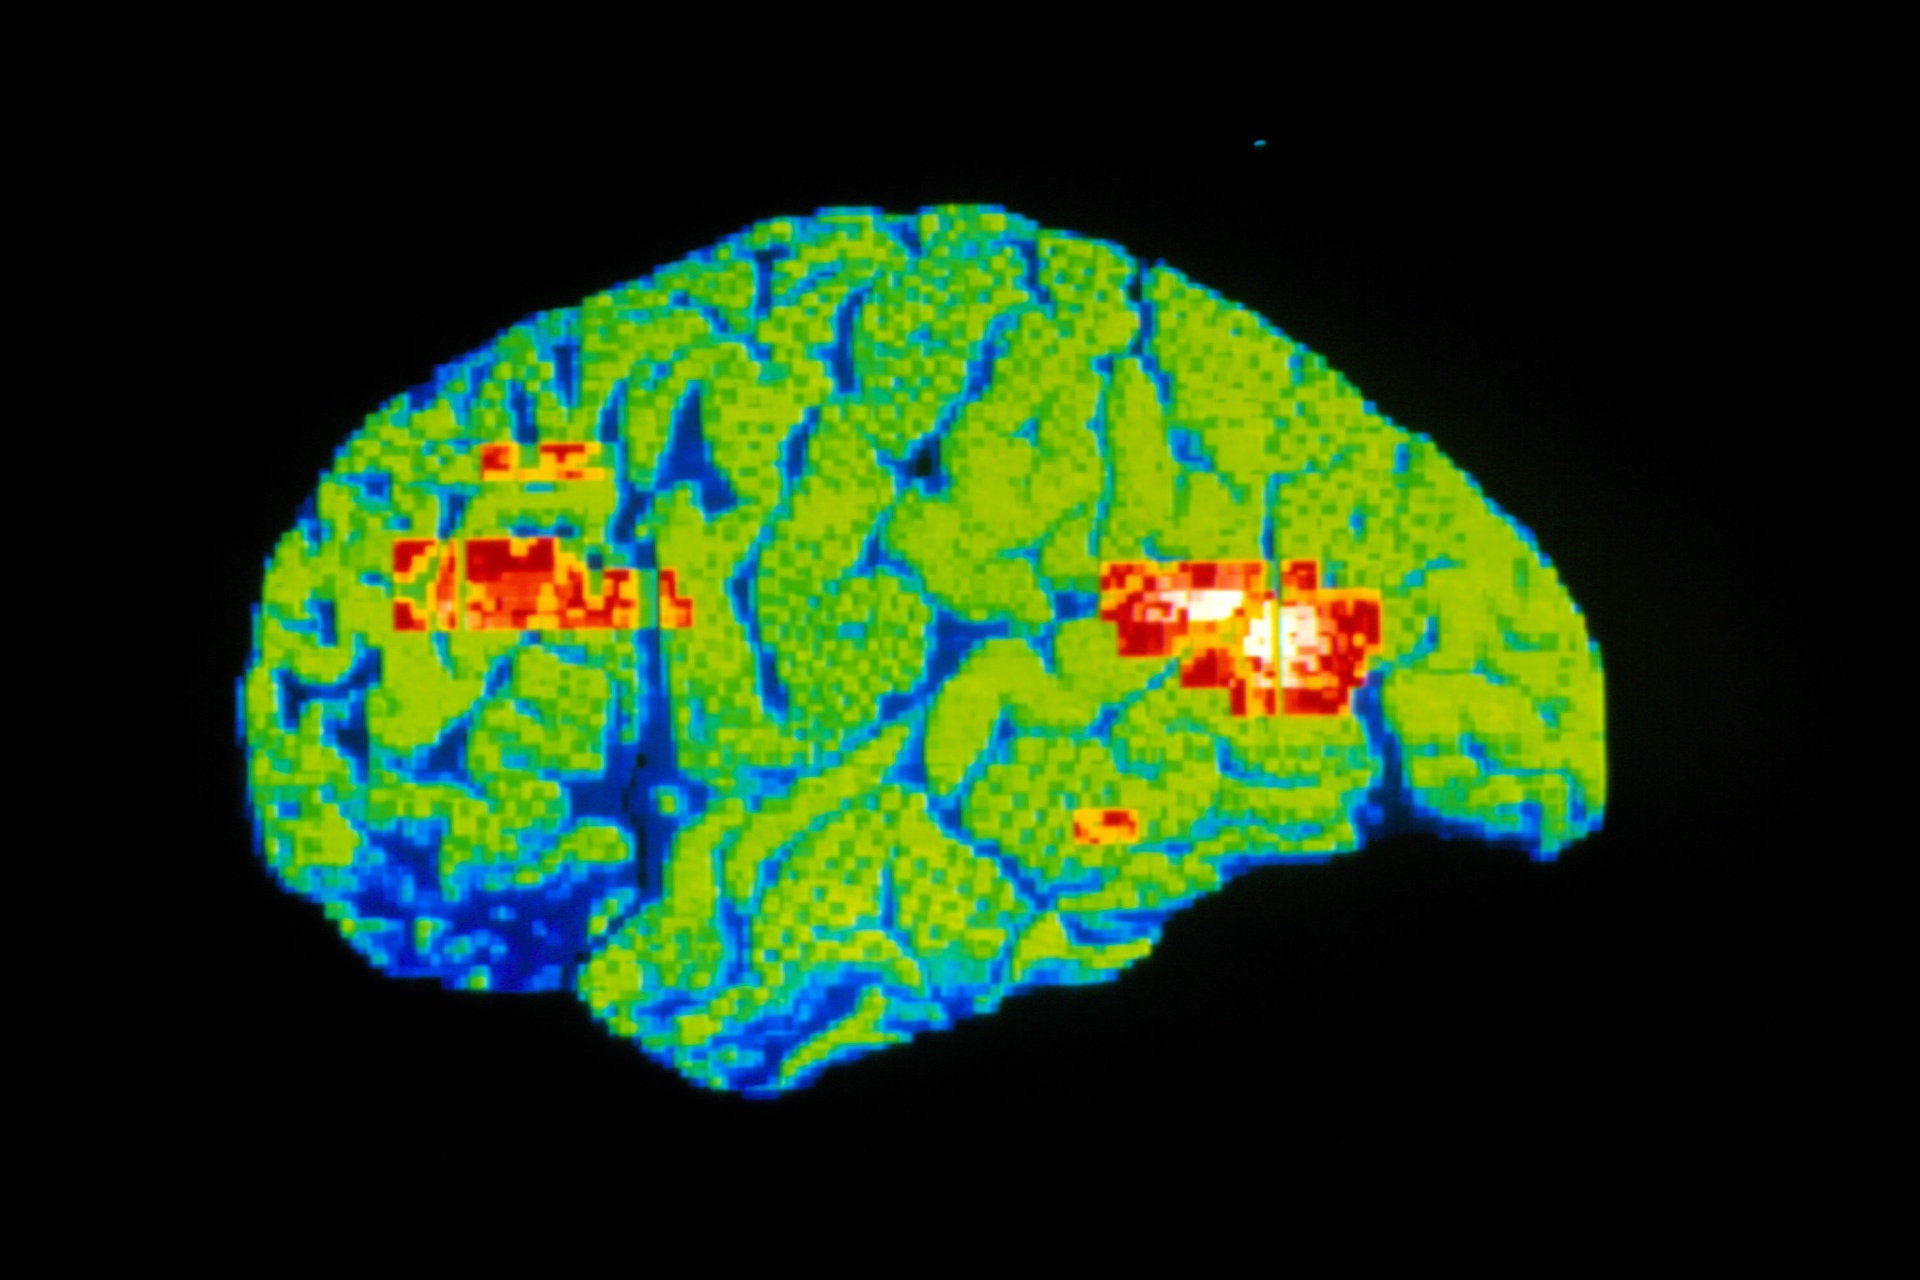

케타민은 마취효과외에 항우울제가 잘 듣지 않는 심한 중증 우울병 환자들의 증상개선에 효과가 있는것으로 알려졌다. 따라서 잘 사용하면 알코올 중독, 헤로인 중독 치료에 도움이 된다는 연구결과가 있으나

개인이 임의로 복용할 경우 신경계의 구조적 영구손상을 일으켜